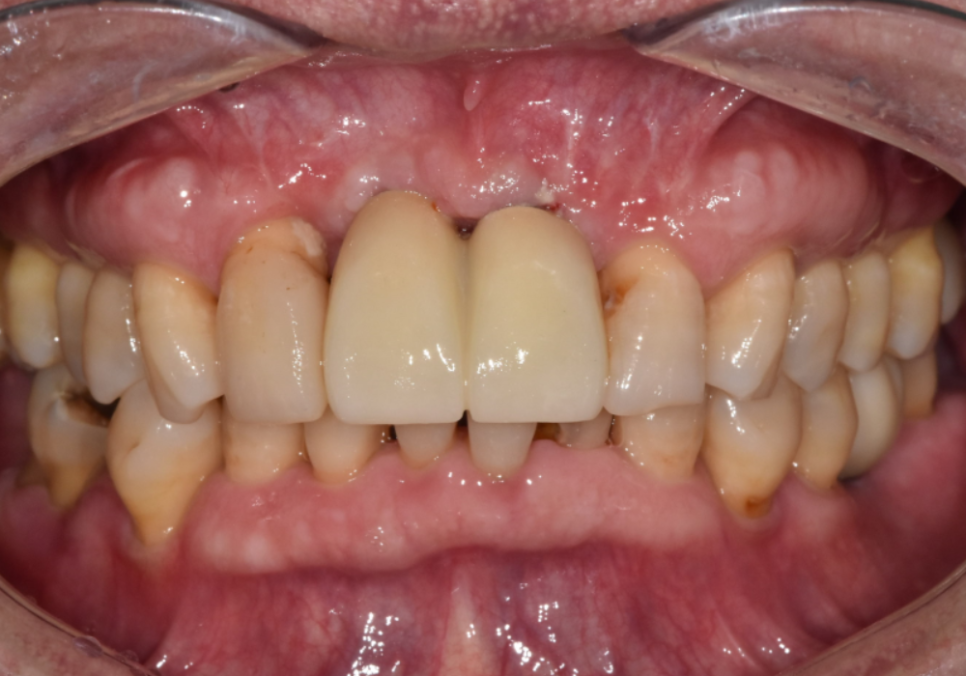

치료 결과

수술 후 4개월이 지나 임플란트와 뼈가

단단히 결합된 것을 확인했습니다.

이제 마지막으로 임플란트

보철물을 만드는 단계를 거치는데요.

240319

꼼꼼하고 정교한 디지털 과정을 거친 덕분에

만족스러운 보철물이 완성되었네요.^^

230524 (전) 240319 (후)